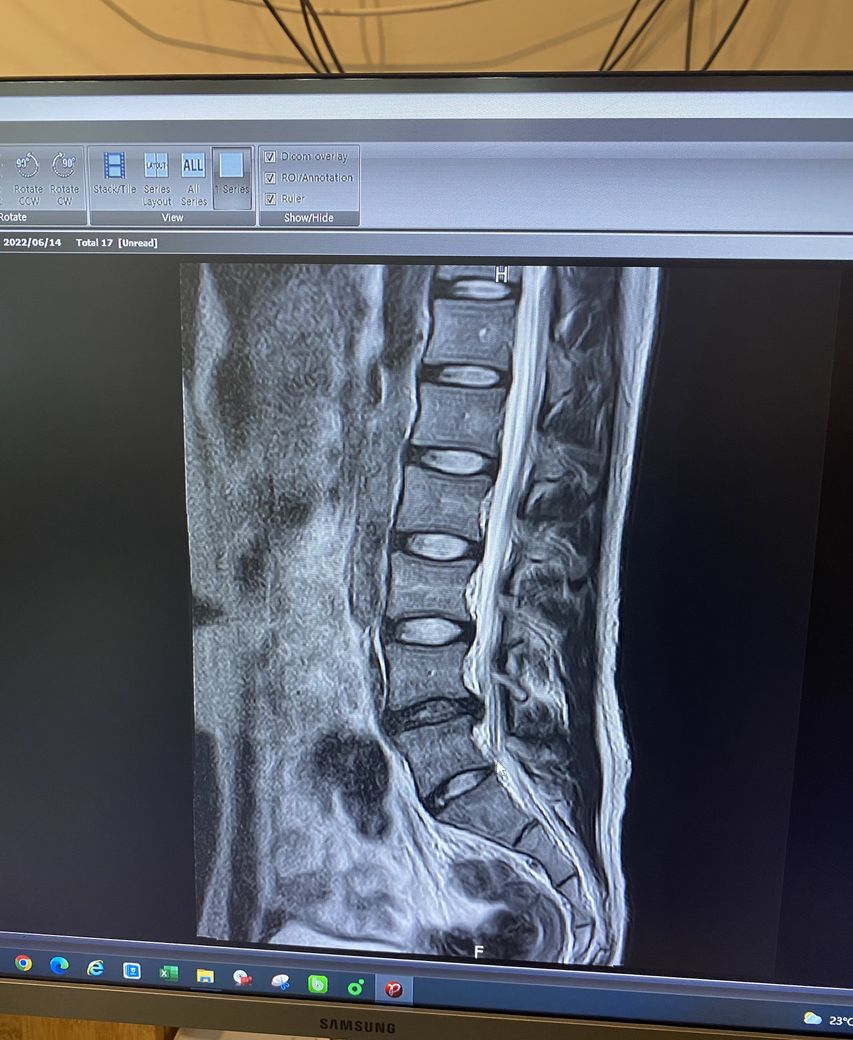

허리디스크 판정 후 6개월동안 침상안정을 취하고 오늘 처음 mri를 찍었습니다.

Mri상 퇴행 및 허리디스크 진행이 심한지?

현재 요추 4-5번 디스크 탈출증으로 인한 방사통이 있으신것 같습니다.

• 올리신 MRI 사진의 소견으로 보았을 때에는 돌출형으로 디스크가 있으며 신경을 꽤 누르고 있습니다. 축영상을 보아야 더 정확한 판단을 내릴 수 있을 것이지만, 증상이 방사통만 살짝 있을 정도라면 경미한 편이며 헬스를 하는 것에 크게 문제될 것 없습니다. 무리가 가지 않는 선에서 헬스와 같은 코어 근육 강화 운동을 해주어서 허리의 부담을 줄이고 디스크 회복을 시도해보시길 권고드립니다.

L4-L5 사이에 디스크 탈출증이 관찰됩니다.

단면도 함께 봐야 정확한 상태를 파악하는게 가능하지만 이 영상만 봐도 상태가 좋지 않음을 알 수 있습니다.

다른 부위의 디스크는 하얀색으로 보이는데 L4-L5 디스크는 색이 많이 검정색으로 보이는것도 수핵이 빠져나갔음을 알 수 있습니다.